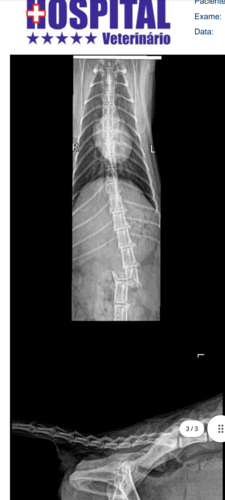

Olá eu sou a Maggie, estava correndo de outro gatinho que estava me incomodando no muro da minha casa, sofri um acidente pois cai do muro e estou precisando urgentemente de uma cirurgia para realinhar minha coluna que está com fratura Interna, já não consigo fazer minhas necessidades sozinha, perdi os movimentos das minhas perninhas traseiras, e todos os dias tomo tramadol de 12h em 12h para não sentir dor, já não posso fazer o que eu amo que correr e nem brincar mais😔